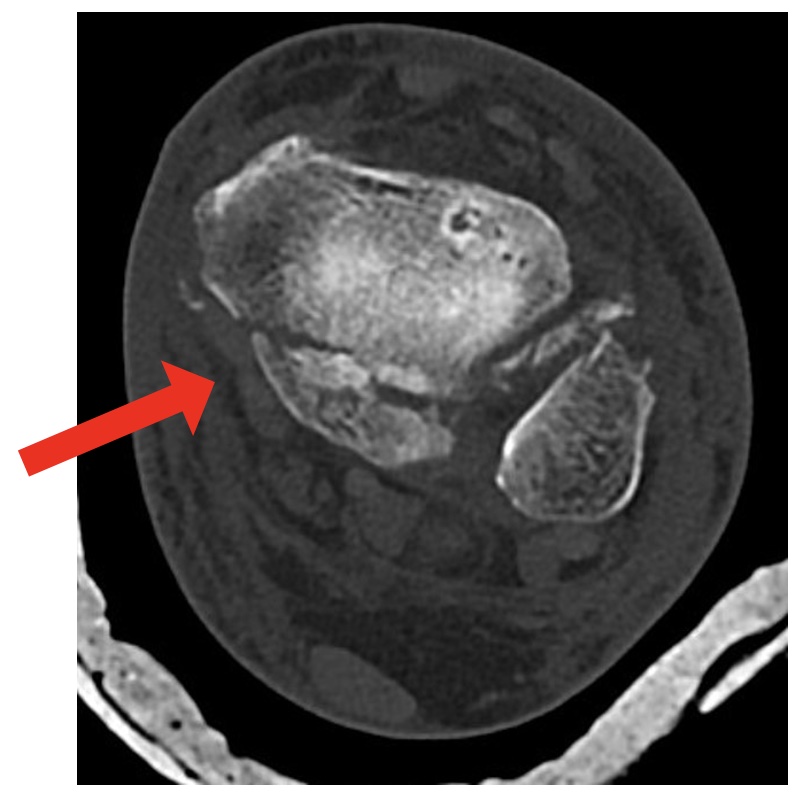

CT scan is the preferred test:

- Fracture configuration

- ‘Die-punch’ fragments

- Intra-articular fragments

Figure 1: Mason & Molloy (2017)